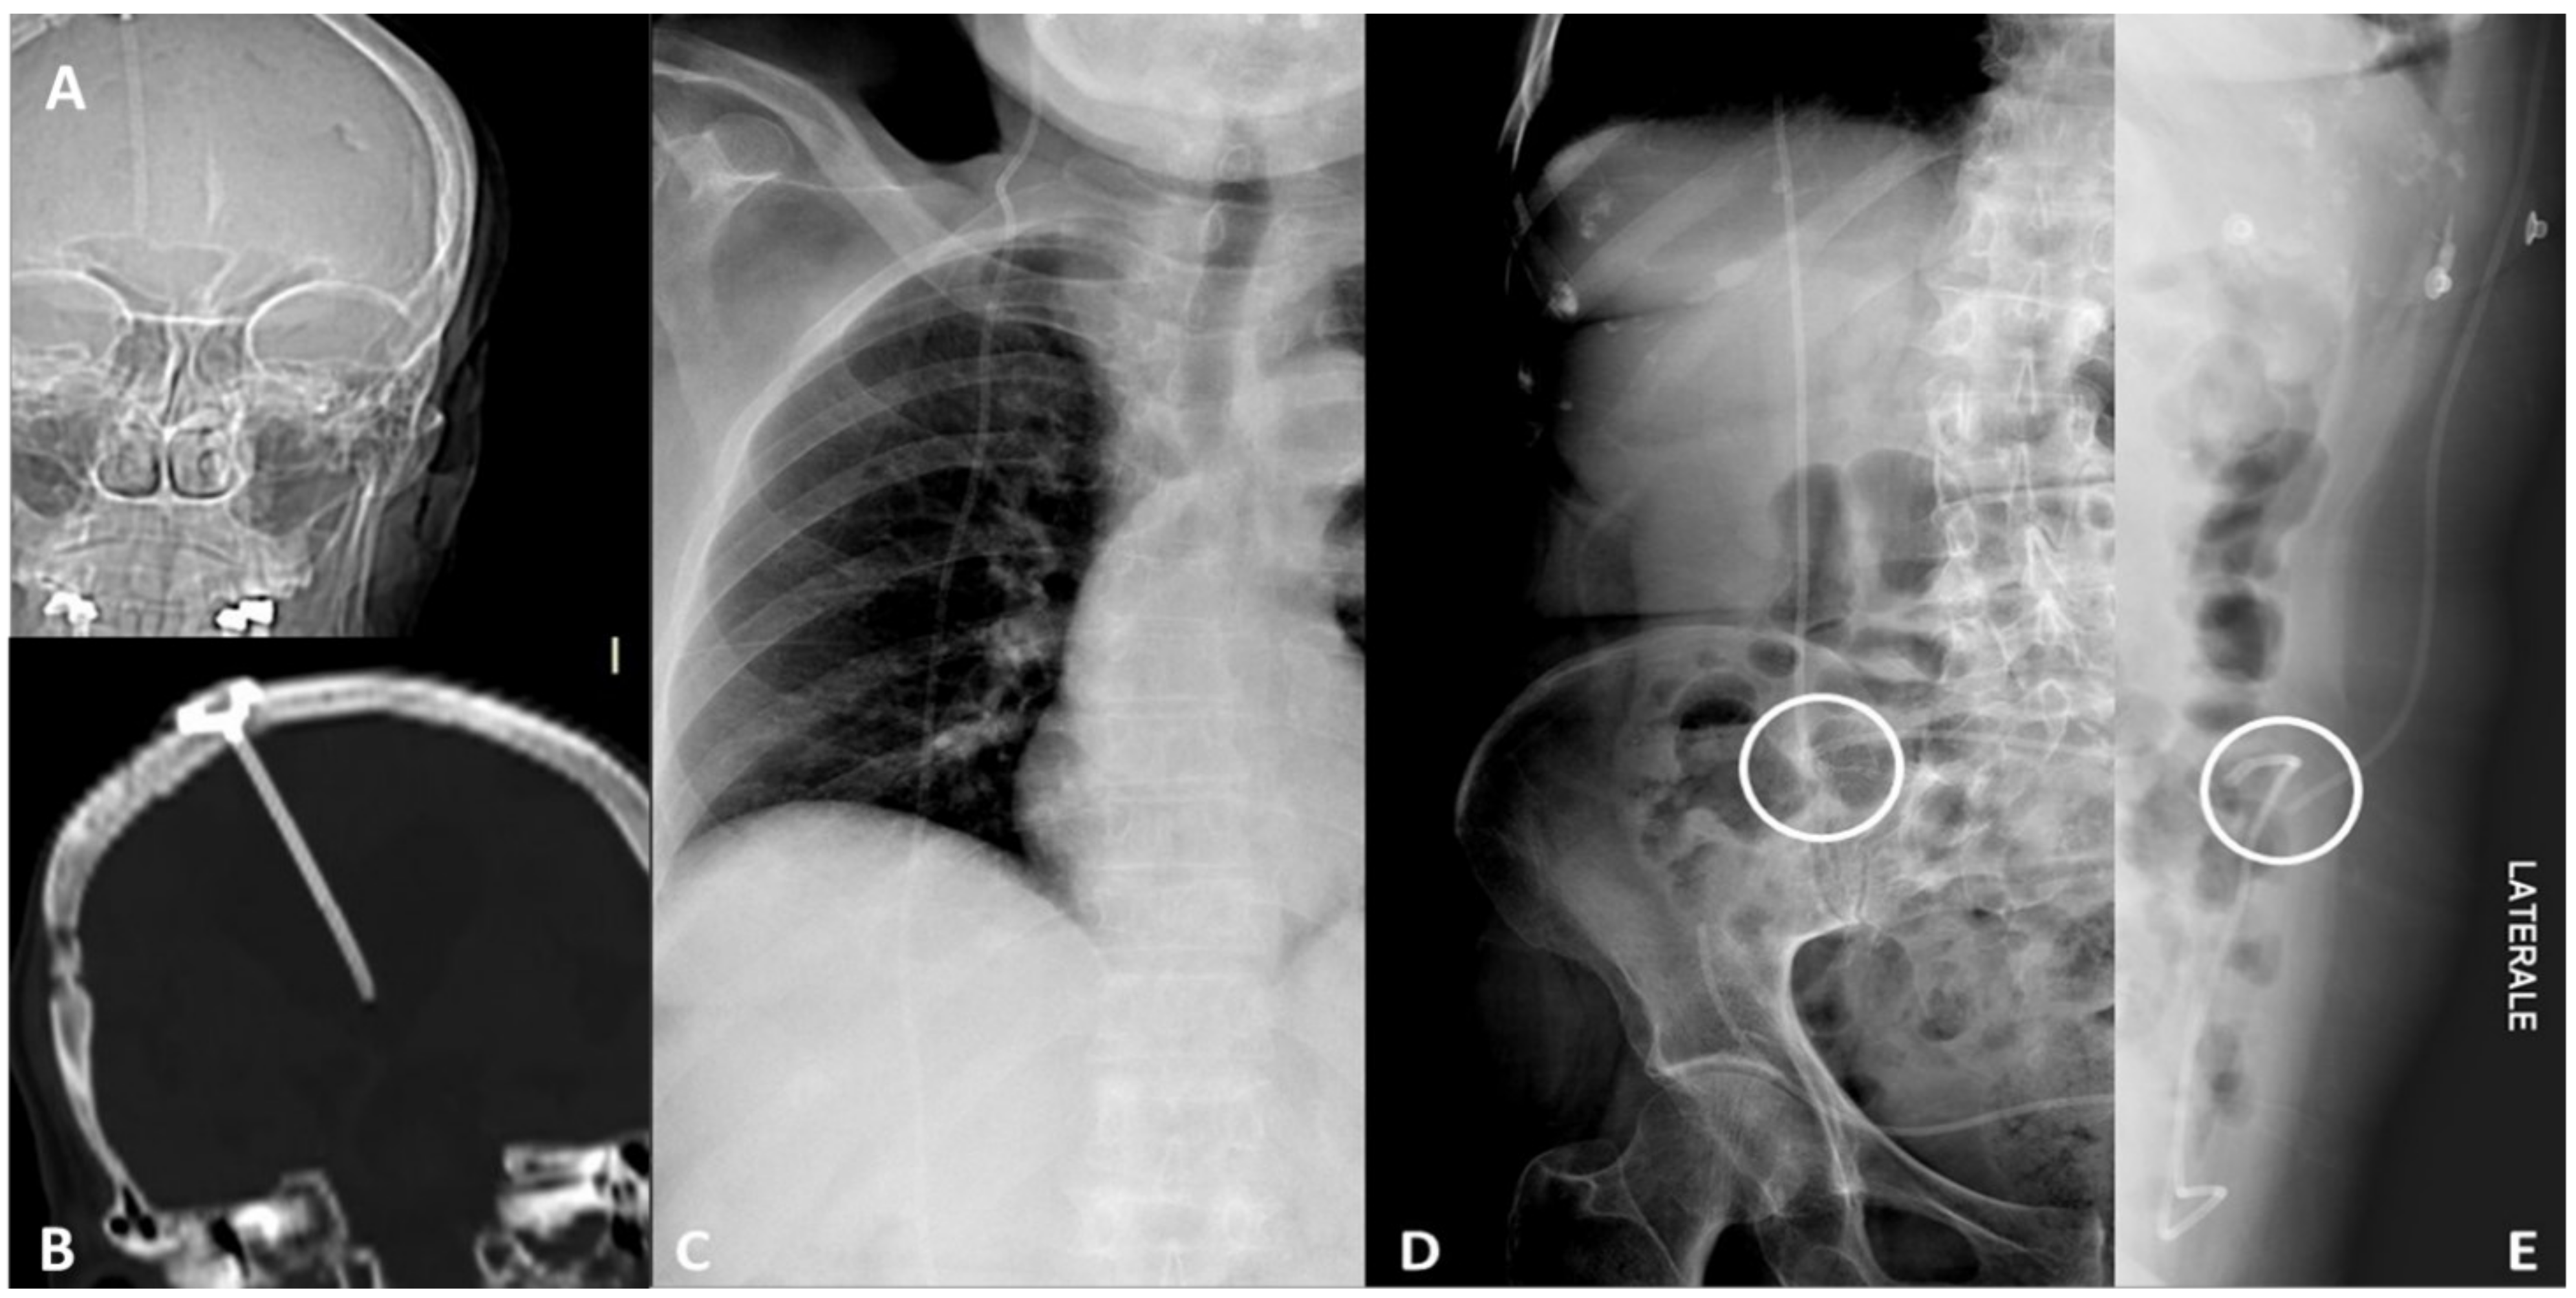

2. Device Identification and Recognition

3. Device Integrity and Migration